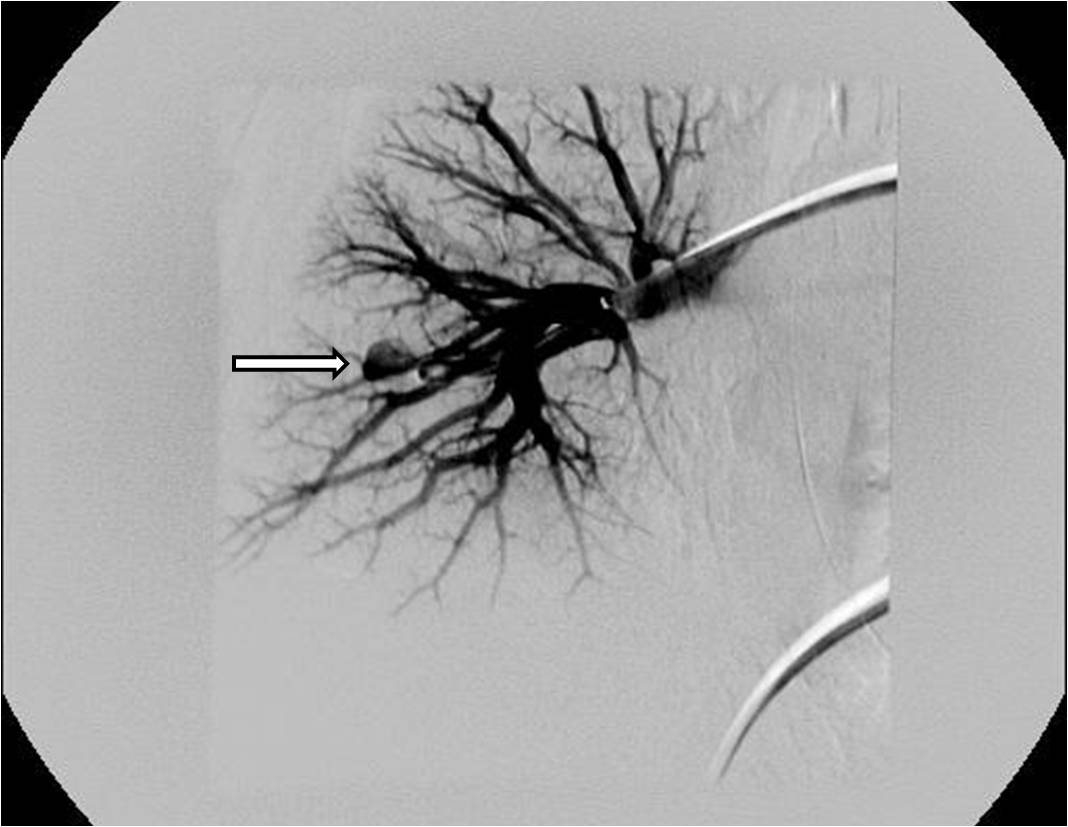

Figures

- Poyanli A, Acunas B, Rozanes I, et al. Endovascular therapy in the management of moderate and massive haemoptysis. Br J Radiol 2007;80:331-336.

- Remy-Jardin M, Bouaziz N, Dumont P, et al. Bronchial and nonbronchial systemic arteries at multi-detector row CT angiography: comparison with conventional angiography. Radiology 2004;233:741-749.

- Swanson KL, Johnson CM, Prakash UB, et al. Bronchial artery embolization : experience with 54 patients. Chest 2002;121:789-795.